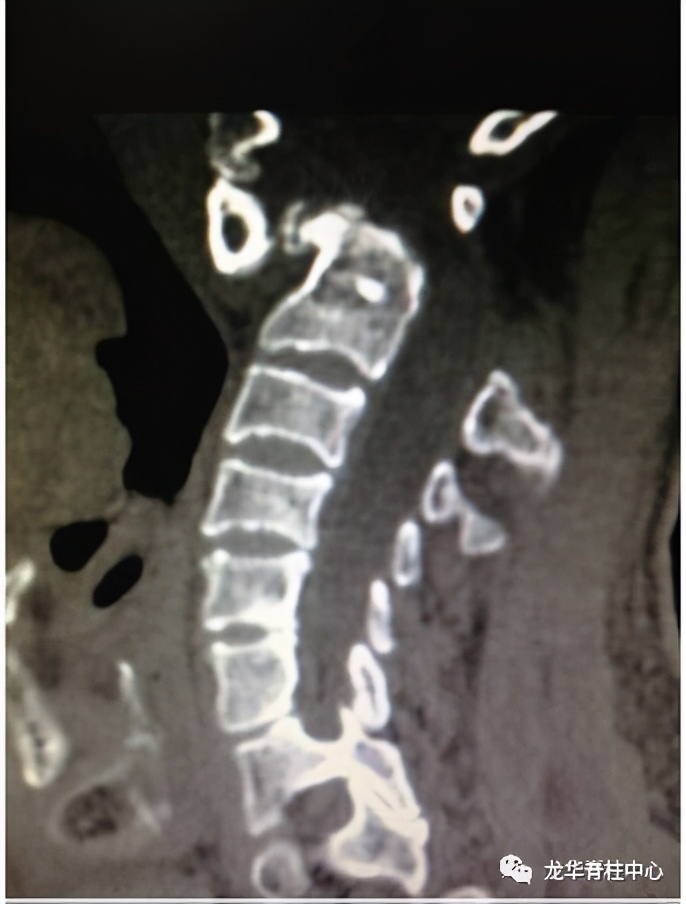

显微镜下寰枢椎脱位经口松解、后路固定术

开展深圳市首例寰枢椎脱位经口咽松解、后路椎弓根钉板内固定术